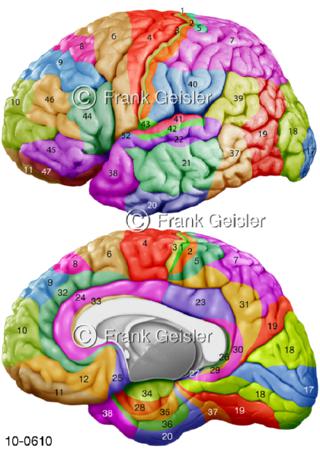

Bildergalerie Nervensystem

Bilder zum Nervensystem,dem Gehirn, Teil des zentralen Nervensystem, Zentralnervensystem ZNSmit Rückenmark, Abbildungen zum Nervengeflecht (Nervenplexus), die Verflechtungen von Nervenfasern, aus der Wirbelsäule hervortretende Nervenäst sowie Nervenzellen der Nerven